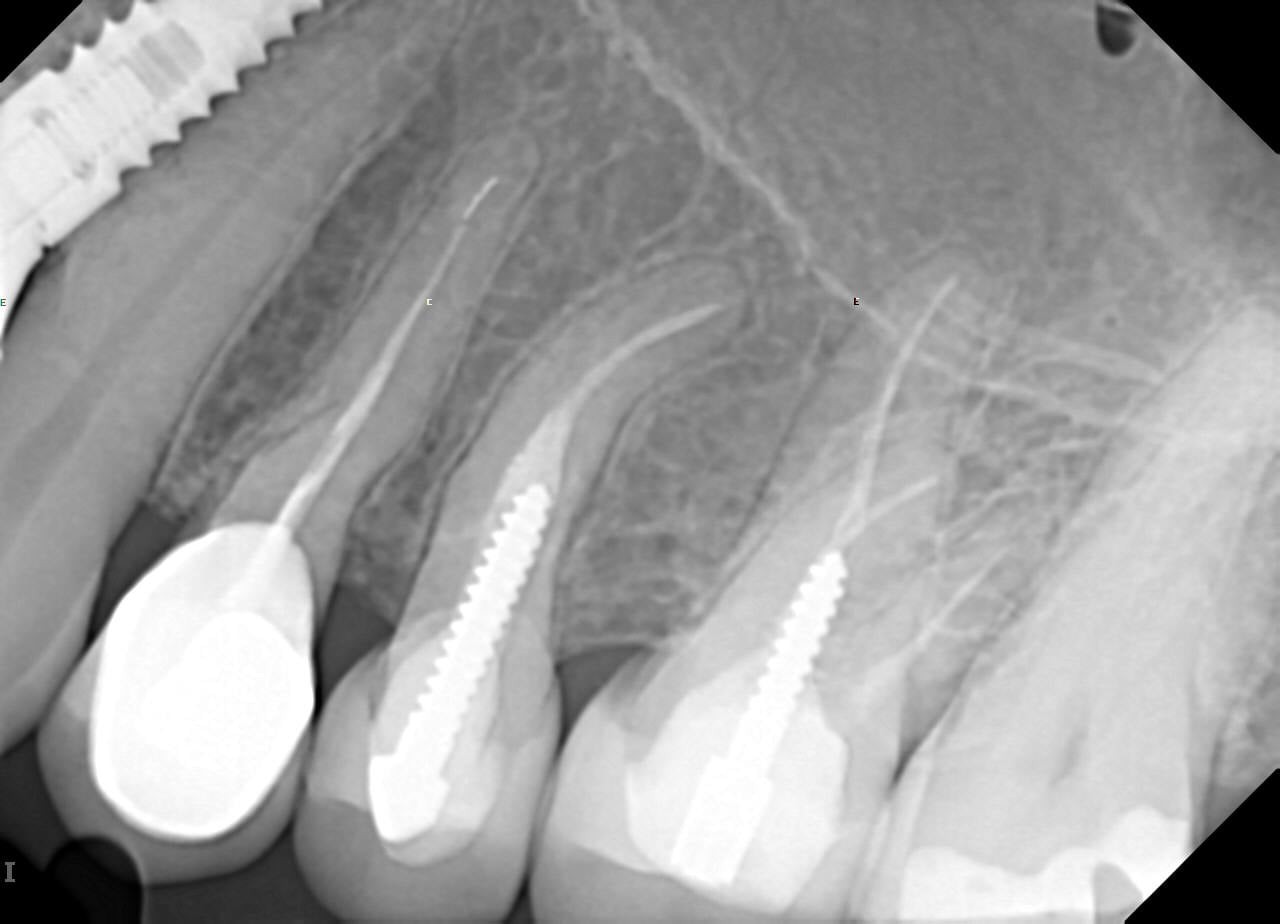

24 / 35

24. On which surface a recurrent caries can be detected?

no recurrent caries can be seen in this X ray